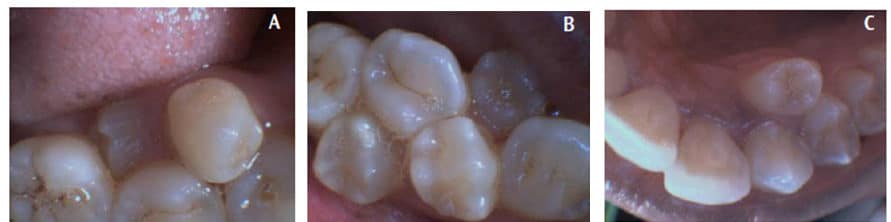

Extraoral examination showed the skeletal arrangement presented with good bilateral symmetry and no abnormalities suggestive of a systemic syndrome. No palpable lymph nodes or extraoral lesions were noted. Prior to an intraoral exam, the patient performed a preprocedural rinse with an antimicrobial essential oils mouthrinse to reduce the number of oral microorganisms present.19 Intraoral examination of hard tissues revealed 39 teeth clinically visible. No other dental anomalies were found. Family history related to supernumerary teeth was noncontributory. In addition to a full complement of teeth, seven supplemental supernumerary teeth were noted in the clinical exam (Figure 1A through Figure 1C). Angle’s Class II occlusion, a slight open bite, a 2-mm overjet, and a 5-mm left shift of midline were noted.

The periodontal classification was determined to be gradual-onset, generalized slight chronic periodontitis, modified by dentition (tooth anatomic factors). Clinical examination revealed no restorations and a large caries lesion on the distal of the upper left second molar, and incipient lesions on the occlusal surfaces of lower-left first and second molars, and lower-right second molar. Panoramic and full-mouth radiographic surveys revealed a lower-left impacted distomolar and lower-right supplemental premolar, and lower-right distomolar (Figure 2 and Figure 3), bringing the number of supernumerary teeth to 10. The patient was noted to have minimal supragingival calculus and generalized heavy subgingival calculus. The visual exam and a disclosing solution revealed only minimal plaque/biofilm accumulation.